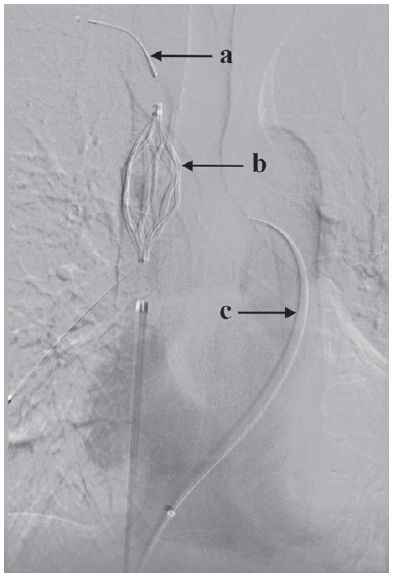

其次,研究人员将PICC管替换为右锁骨下静脉溶栓导管,将导管尖置于上腔静脉(图1),分别通过两根导管注射10万IU剂量的尿激酶。术后将10万IU/24h/导管的低剂量尿激酶持续泵入导管,对导管鞘肝素化处理。每日检测血液学指标,包括血红蛋白、血小板、活化部分凝血活酶时间(APTT)和纤维蛋白原,以监测和避免出血风险。

图1 数字减影血管造影(DSA)分别显示右锁骨下静脉溶栓导管(a)、上腔静脉滤器(b)、右肺动脉干导管(c)